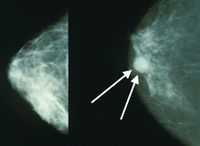

سرطان الثدي

مقالة مفصلة: سرطان الثدي

مقالة مفصلة: سرطان الثدي

| سرطان الثدي | ||

| معدل الانتشار | 2.1 مليون (2015) | |

| معدل البقاء 5 سنوات | ~85% (الولايات المتحدة والمملكة المتحدة)[4] [5] | |

| حالات الوفاة | 533.600 (2015)[6] | |

| عوامل الخطورة | طفرات موروثة في الجين BRCA1 أو الجين BRCA2؛ تقدم العمر؛ البدء المبكر للحيض؛ تأخر الإياس (سن اليأس)، عدم إنجاب أي طفل أو إنجاب الطفل الأول بعد سن الثلاثين؛ التاريخ الشخصي personal history أو العائلي للإصابة بسرطان الثدي؛ وربما يكون للغذاء الغني بالدهون دور في ذلك. تنخفض معدلات الوفيات بين النساء البيض ولا سيما اللواتي تقل أعمارهن عن الخامسة والستين. | |

| العلامات المنذرة | وجود كتلة غير مؤلمة في الثدي هو علامة نموذجية، وقد تكون مؤلمة أحيانا؛ أي تغير في لون أو شكل أو طبيعة نسيج الثدي أو الحلمة؛ إفراز discharge من الحلمة أو التألم عند جَسِّها. | |

| الكشف والتشخيص | الفحص الذاتي والفحوص السريرية للثدي، تصوير الثدي الشعاعي mammogram. ينصح الخبراء أن يُجرى سنويا تصوير شعاعي وفحص عام للثدي لجميع النساء اللواتي تتجاوز أعمارهن الخمسين، بل ولبعض النساء الأصغر أيضاً.

| |

| العلاج | يمكن أن يكون الاستئصال الكامل للثدي mastectomy مناسبا للأورام الموضّعة. وقد يفضل في كثير من الأحيان الجراحة المحافظة على الثدي breast-conserving surgery (بإزالة الورم وبعض النسج المحيطة به وتسمى أحياناً استئصال الكتلة lumpectomy) متبوعة بمعالجة شعاعية موضعية. وعلى الرغم من أن نسبة المعاودة (الانتكاس) أكبر في الجراحة المحافظة على الثدي، فإن هذه المعاودات يمكن علاجها باستئصال الثدي كاملا. وعلى كل حال، فإن نسبة البُقيا في هذه الحالة مساوية للحالات التي تعالج باستئصال الثدي في البداية. وقد يُتبع كل من الإجراءين بمعالجة كيميائية إضافية أو بمعالجة حاصرة للهرمونات. وإذا كانت الخلايا الورمية تحوي مستويات عالية من مستقبلات هرمونات الإستروجين والپروجسترون فإن هذا مؤشر جيد، إذ تستطيع المعالجة الحاصرة للهرمونات إيقاف نمو هذه الخلايا.

| |

| ملاحظات | آراء خلافية: على الرغم من أن الفحوص التي تُجرى للكشف عن الطفرات الوراثية في الجينيْن BRCA1 و BRCA2 قد صارت متوافرة، فإن الأطباء لم يصلوا إلى إجماع على استخدام هذه الفحوص. كما أن جدوى إجراء المعالجة الكيميائية عند المريضات المسنّات وجدوى تصوير الثدي الشعاعي الروتيني لمن لم يَبْلغن سن الخمسين، ما زالتا موضع جدل. وتشير بعض الدراسات إلى أن المعالجة الجراحية لسرطان الثدي خلال النصف الثاني من الدورة الطمثية للمريضة قد تعطي نتائج أفضل. | |